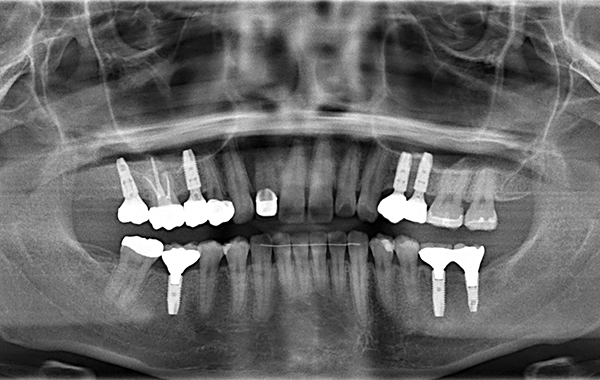

術前、術後のパノラマX線写真です。MTMをする事で歯が本来の位置に戻り、インプラントも理想的な位置に埋入することが出来ました。

奥歯の噛み合わせに目を向けてみると、歯が挺出しており、このままでは被せ物を入れることが出来ません。そこで圧下をしていくのと同時に隙間や歯が傾斜しているところをMTM(小矯正)で治し、入れ歯は噛みづらくて違和感があるとのことでインプラント治療をしていくこととしました。

奥歯がない状態が続いてしまうと前歯に負担がかかり、結果また抜けていってしまうという負の連鎖が起こってしまいます。

奥歯がしっかりと安定する事で、負の連鎖を食い止めることが出来ます。